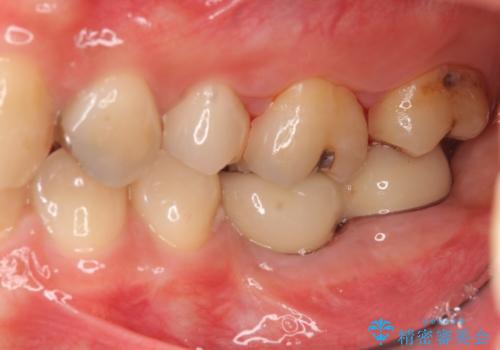

- 90万円(ストローマンインプラント・骨造成・チタンカスタムアバットメント・ジルコニアクラウン×2)費用は治療当時の料金となります

インプラントを用いて機能回復を行うことで、奥歯がしっかりと噛めるようになります。

周囲に骨があることでより長期的な予後を見込むことができます。